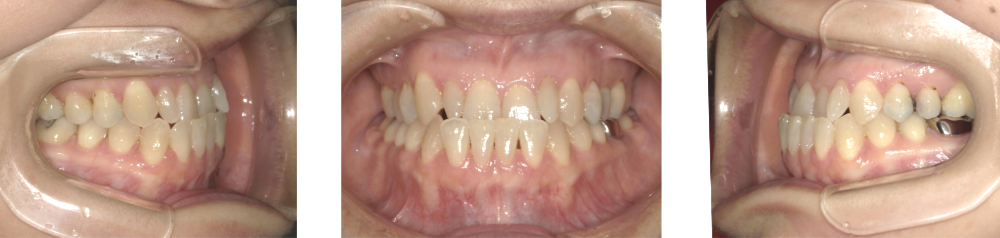

軽度受け口症例画像

軽度(前歯の一部だけが反対咬合)の方の場合

軽度の受け口は、上下の前歯の前後差があまり大きくなく、前歯の一部だけが反対に噛んでいる状態です。 見た目にはあまり気にならないことが多いですが、「前歯で噛み切りにくい」「言いにくい音がある」といったお悩みが出てくることもあります。

治療方法としては、ワイヤー矯正やマウスピース型矯正装置を使って、上の前歯を前に、下の前歯を内側に動かし、前歯のかみ合わせを整えます。奥歯のかみ合わせが大きく乱れていない場合は、非抜歯で治療が進むことが多いです。

治療期間の目安は約6か月〜1年程度で、負担をかけずに前歯の反対かみ合わせを改善し、口元や噛みやすさの改善を目指します。